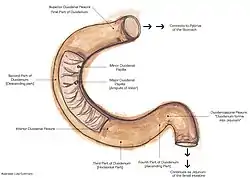

Diagram of the human duodenum with major parts labelled | |

In humans, the duodenum is a hollow jointed tube about 25–38 centimetres (10–15 inches) long connecting the stomach to the middle part of the small intestine.[3][4] It begins with the duodenal bulb and ends at the suspensory muscle of duodenum.[5] Duodenum can be divided into four parts: the first (superior), the second (descending), the third (transverse) and the fourth (ascending) parts.[4]

In humans, the duodenum is a C-shaped hollow jointed tube, 25–38 centimetres (10–15 inches) in length, lying adjacent to the stomach (and connecting it to the small intestine). It is divided anatomically into four sections. The first part lies within the peritoneum but its other parts are retroperitoneal.[8]: 273

The first part, or superior part, of the duodenum is a continuation from the pylorus to transpyloric plane. It is superior to the rest of the segments, at the vertebral level of L1. The duodenal bulb, about 2 cm (3⁄4 in) long, is the first part of the duodenum and is slightly dilated. The duodenal bulb is a remnant of the mesoduodenum, a mesentery that suspends the organ from the posterior abdominal wall in fetal life.[9] The first part of the duodenum is mobile, and connected to the liver by the hepatoduodenal ligament of the lesser omentum. The first part of the duodenum ends at the corner, the superior duodenal flexure.[8]: 273

The second part, or descending part, of the duodenum begins at the superior duodenal flexure. It goes inferior to the lower border of vertebral body L3, before making a sharp turn medially into the inferior duodenal flexure, the end of the descending part.[8]: 274

The pancreatic duct and common bile duct enter the descending duodenum, through the major duodenal papilla. The second part of the duodenum also contains the minor duodenal papilla, the entrance for the accessory pancreatic duct. The junction between the embryological foregut and midgut lies just below the major duodenal papilla.[8]: 274

The third part, or horizontal part or inferior part of the duodenum is 10~12 cm in length. It begins at the inferior duodenal flexure and passes transversely to the left, passing in front of the inferior vena cava, abdominal aorta and the vertebral column. The superior mesenteric artery and vein are anterior to the third part of duodenum.[8]: 274 This part may be compressed between the aorta and SMA causing superior mesenteric artery syndrome.

The fourth part, or ascending part, of the duodenum passes upward, joining with the jejunum at the duodenojejunal flexure. The fourth part of the duodenum is at the vertebral level L3, and may pass directly on top, or slightly to the left, of the aorta.[8]: 274